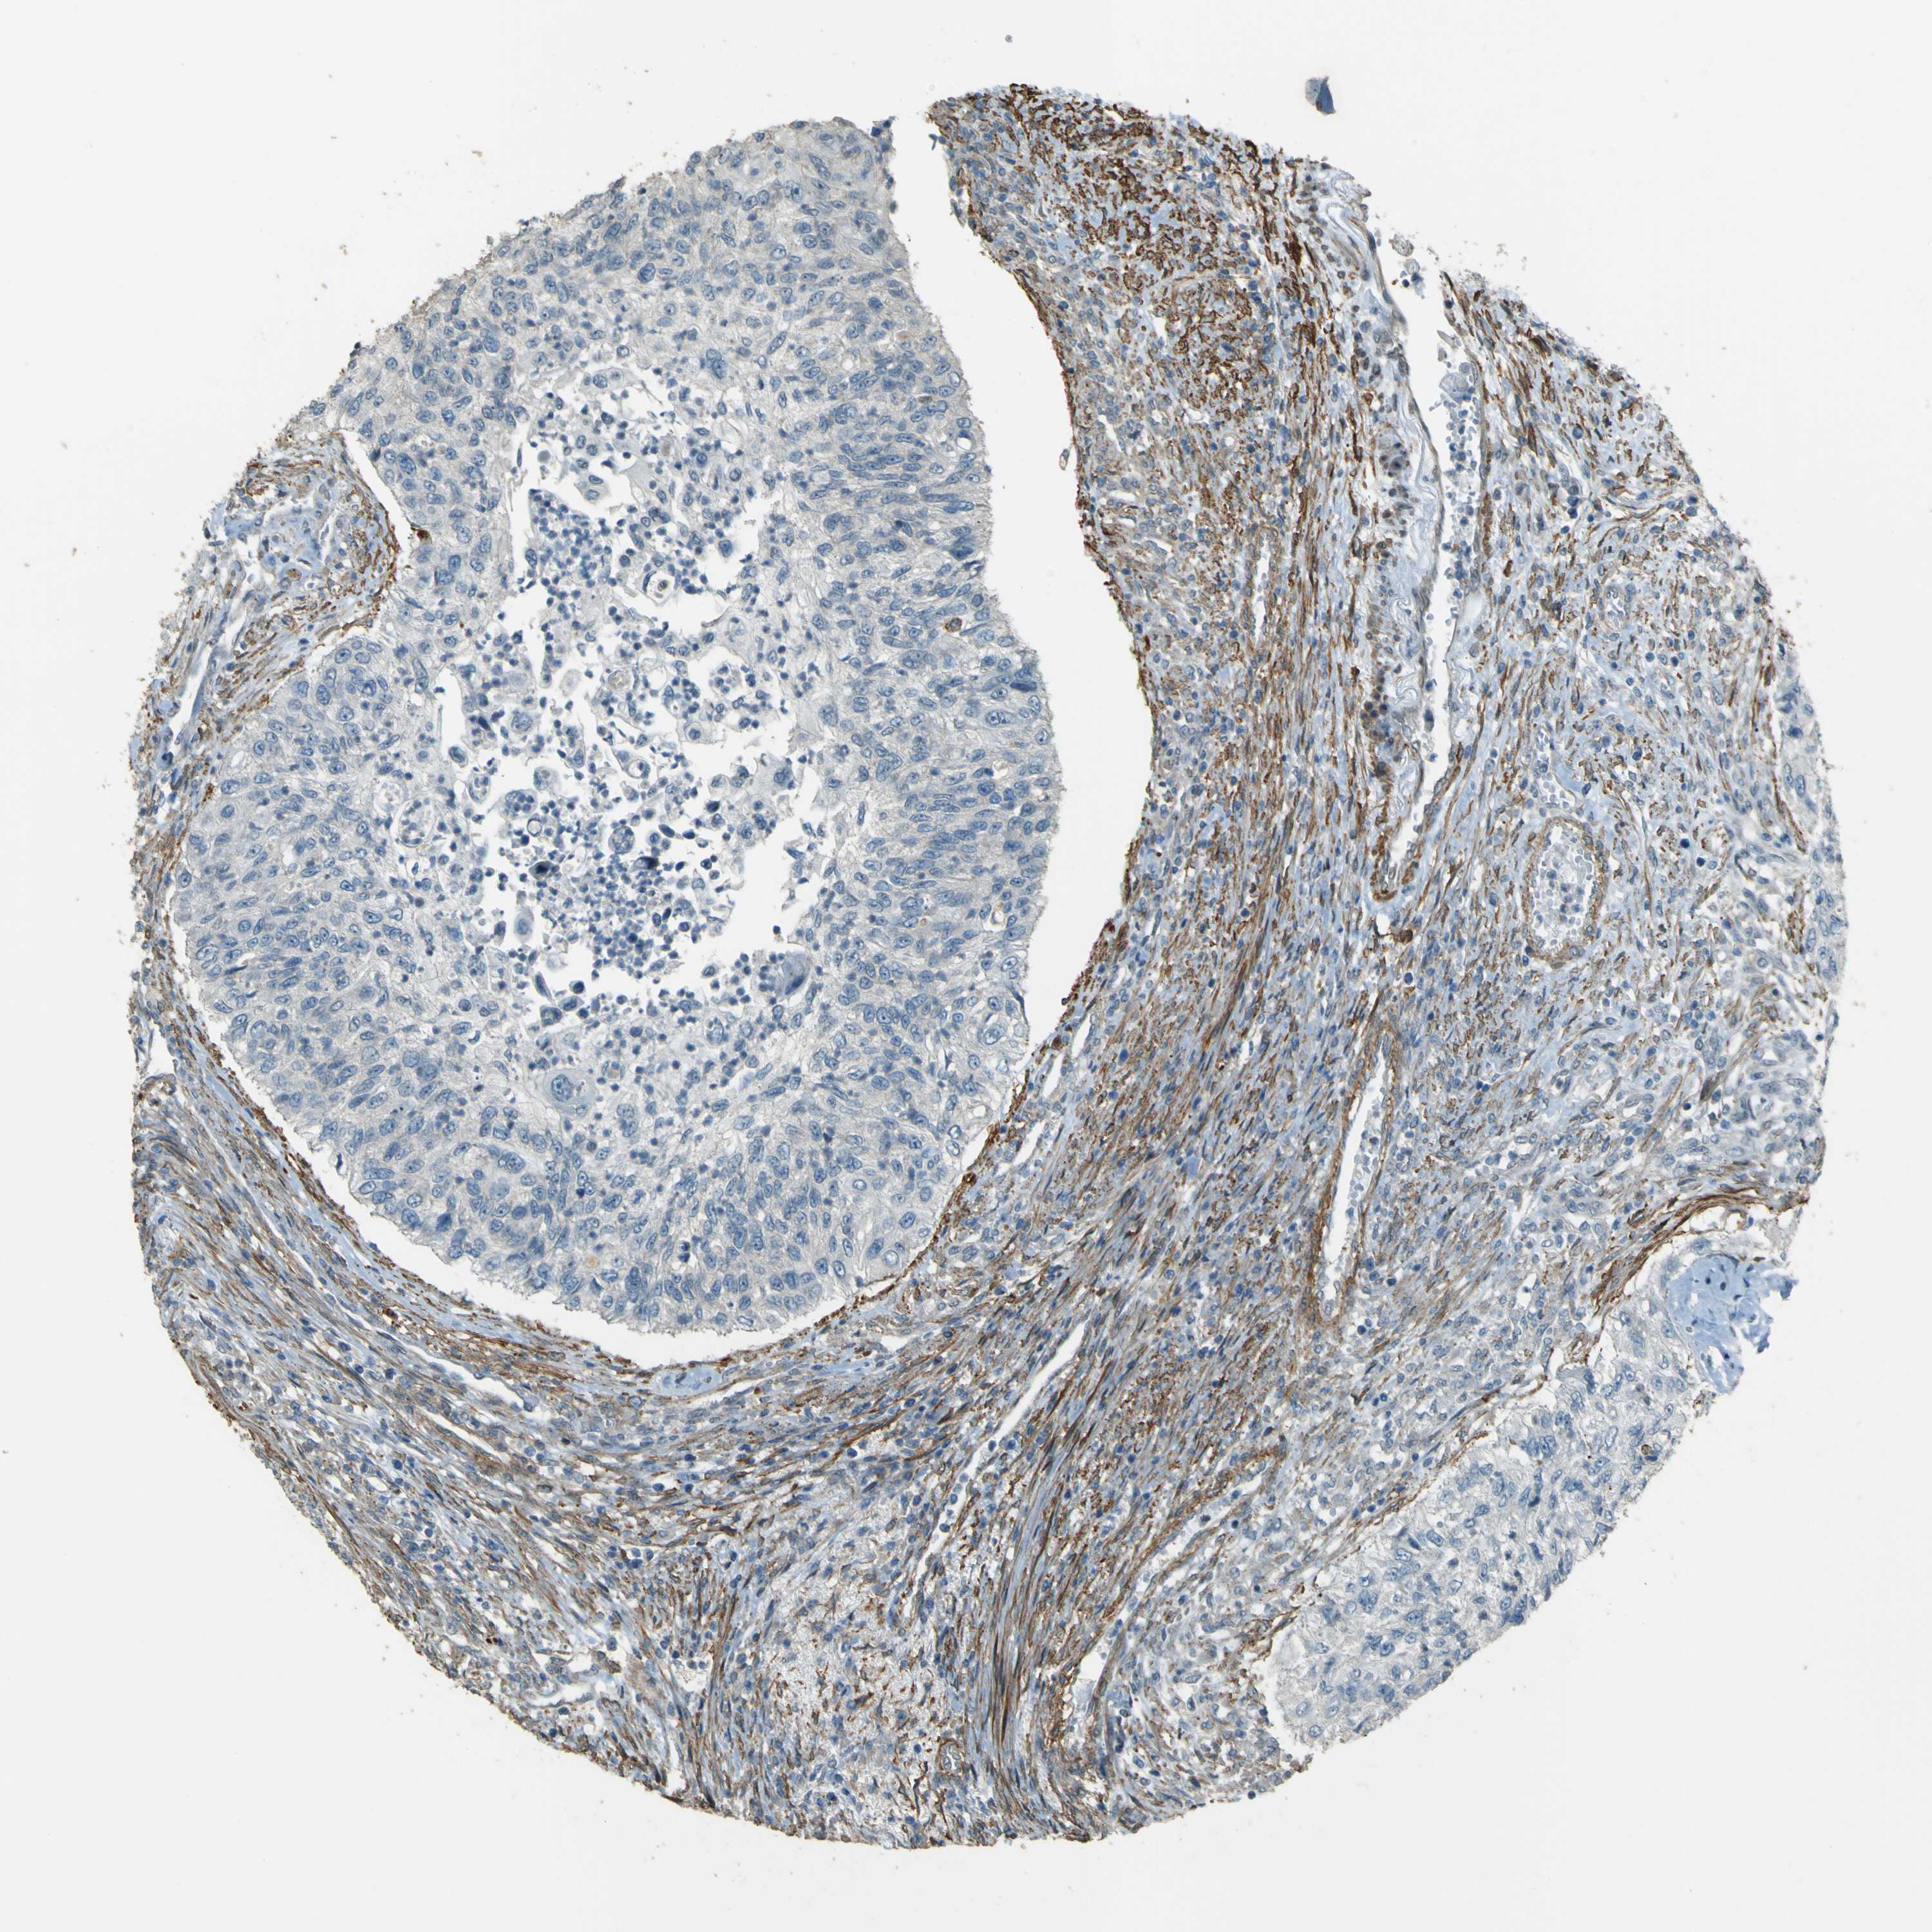

UROTHELIAL CANCER - Protein expressioni

A mouse-over function shows sample information and annotation data. Click on an image to view it in a full screen mode. Samples can be filtered based on level of antibody staining by selecting one or several of the following categories: high, medium, low and not detected. The assay and annotation is described here.

Note that samples used for immunohistochemistry by the Human Protein Atlas do not correspond to samples in the TCGA dataset.

Antibody stainingi

Antibody staining in the annotated cell types in the current human tissue is reported as not detected, low, medium, or high, based on conventional immunohistochemistry profiling in selected tissues. This score is based on the combination of the staining intensity and fraction of stained cells.

Each image is clickable and will lead to virtual microscopy that enables deeper exploration of all samples and also displays staining intensity scores, fraction scores and subcellular localization as well as patient and tissue information for each sample.

Antibody HPA011185

Urothelial carcinoma, Low grade

Urothelial carcinoma, High grade